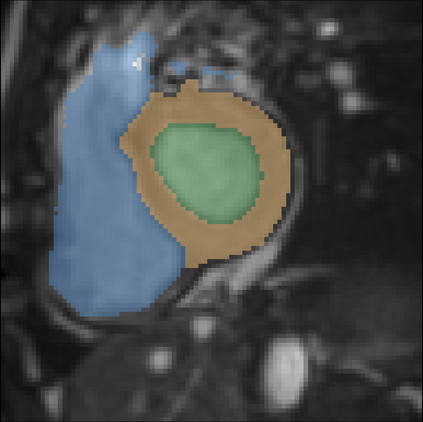

It is imperative to ensure the robustness of deep learning models in critical applications such as, healthcare. While recent advances in deep learning have improved the performance of volumetric medical image segmentation models, these models cannot be deployed for real-world applications immediately due to their vulnerability to adversarial attacks. We present a 3D frequency domain adversarial attack for volumetric medical image segmentation models and demonstrate its advantages over conventional input or voxel domain attacks. Using our proposed attack, we introduce a novel frequency domain adversarial training approach for optimizing a robust model against voxel and frequency domain attacks. Moreover, we propose frequency consistency loss to regulate our frequency domain adversarial training that achieves a better tradeoff between model's performance on clean and adversarial samples. Code is publicly available at https://github.com/asif-hanif/vafa.